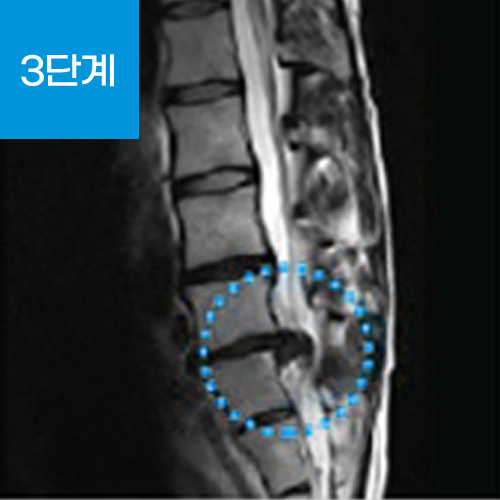

추간판(디스크) 중심에는 수핵과 수핵을 감싸는 섬유륜이라는 막으로 구성되어 있는데 추간판 탈출증이란 척추 뼈와 뼈 사이에서 완충 작용을 해주는 추간판(디스크)이 퇴행성 변화나 외상 등으로 추간판의 탄력이 저하되거나 손상되었을 때 수핵이 척추 바깥으로 탈출(튀어나옴)하게 되어 신경을 압박하여 통증을 느끼는 질환입니다.

손상된 디스크는 주변 신경을 자극하여 통증을 유발하는데 이것을 소위 '디스크'라 불리는 '추간판 탈출증'입니다.